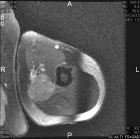

72 year old man left upper arm mass x1 month, accompanied by worsening, constant, dull, minimal pain and tenderness.

No injury

Zoom image: Radiological image Radiological image.